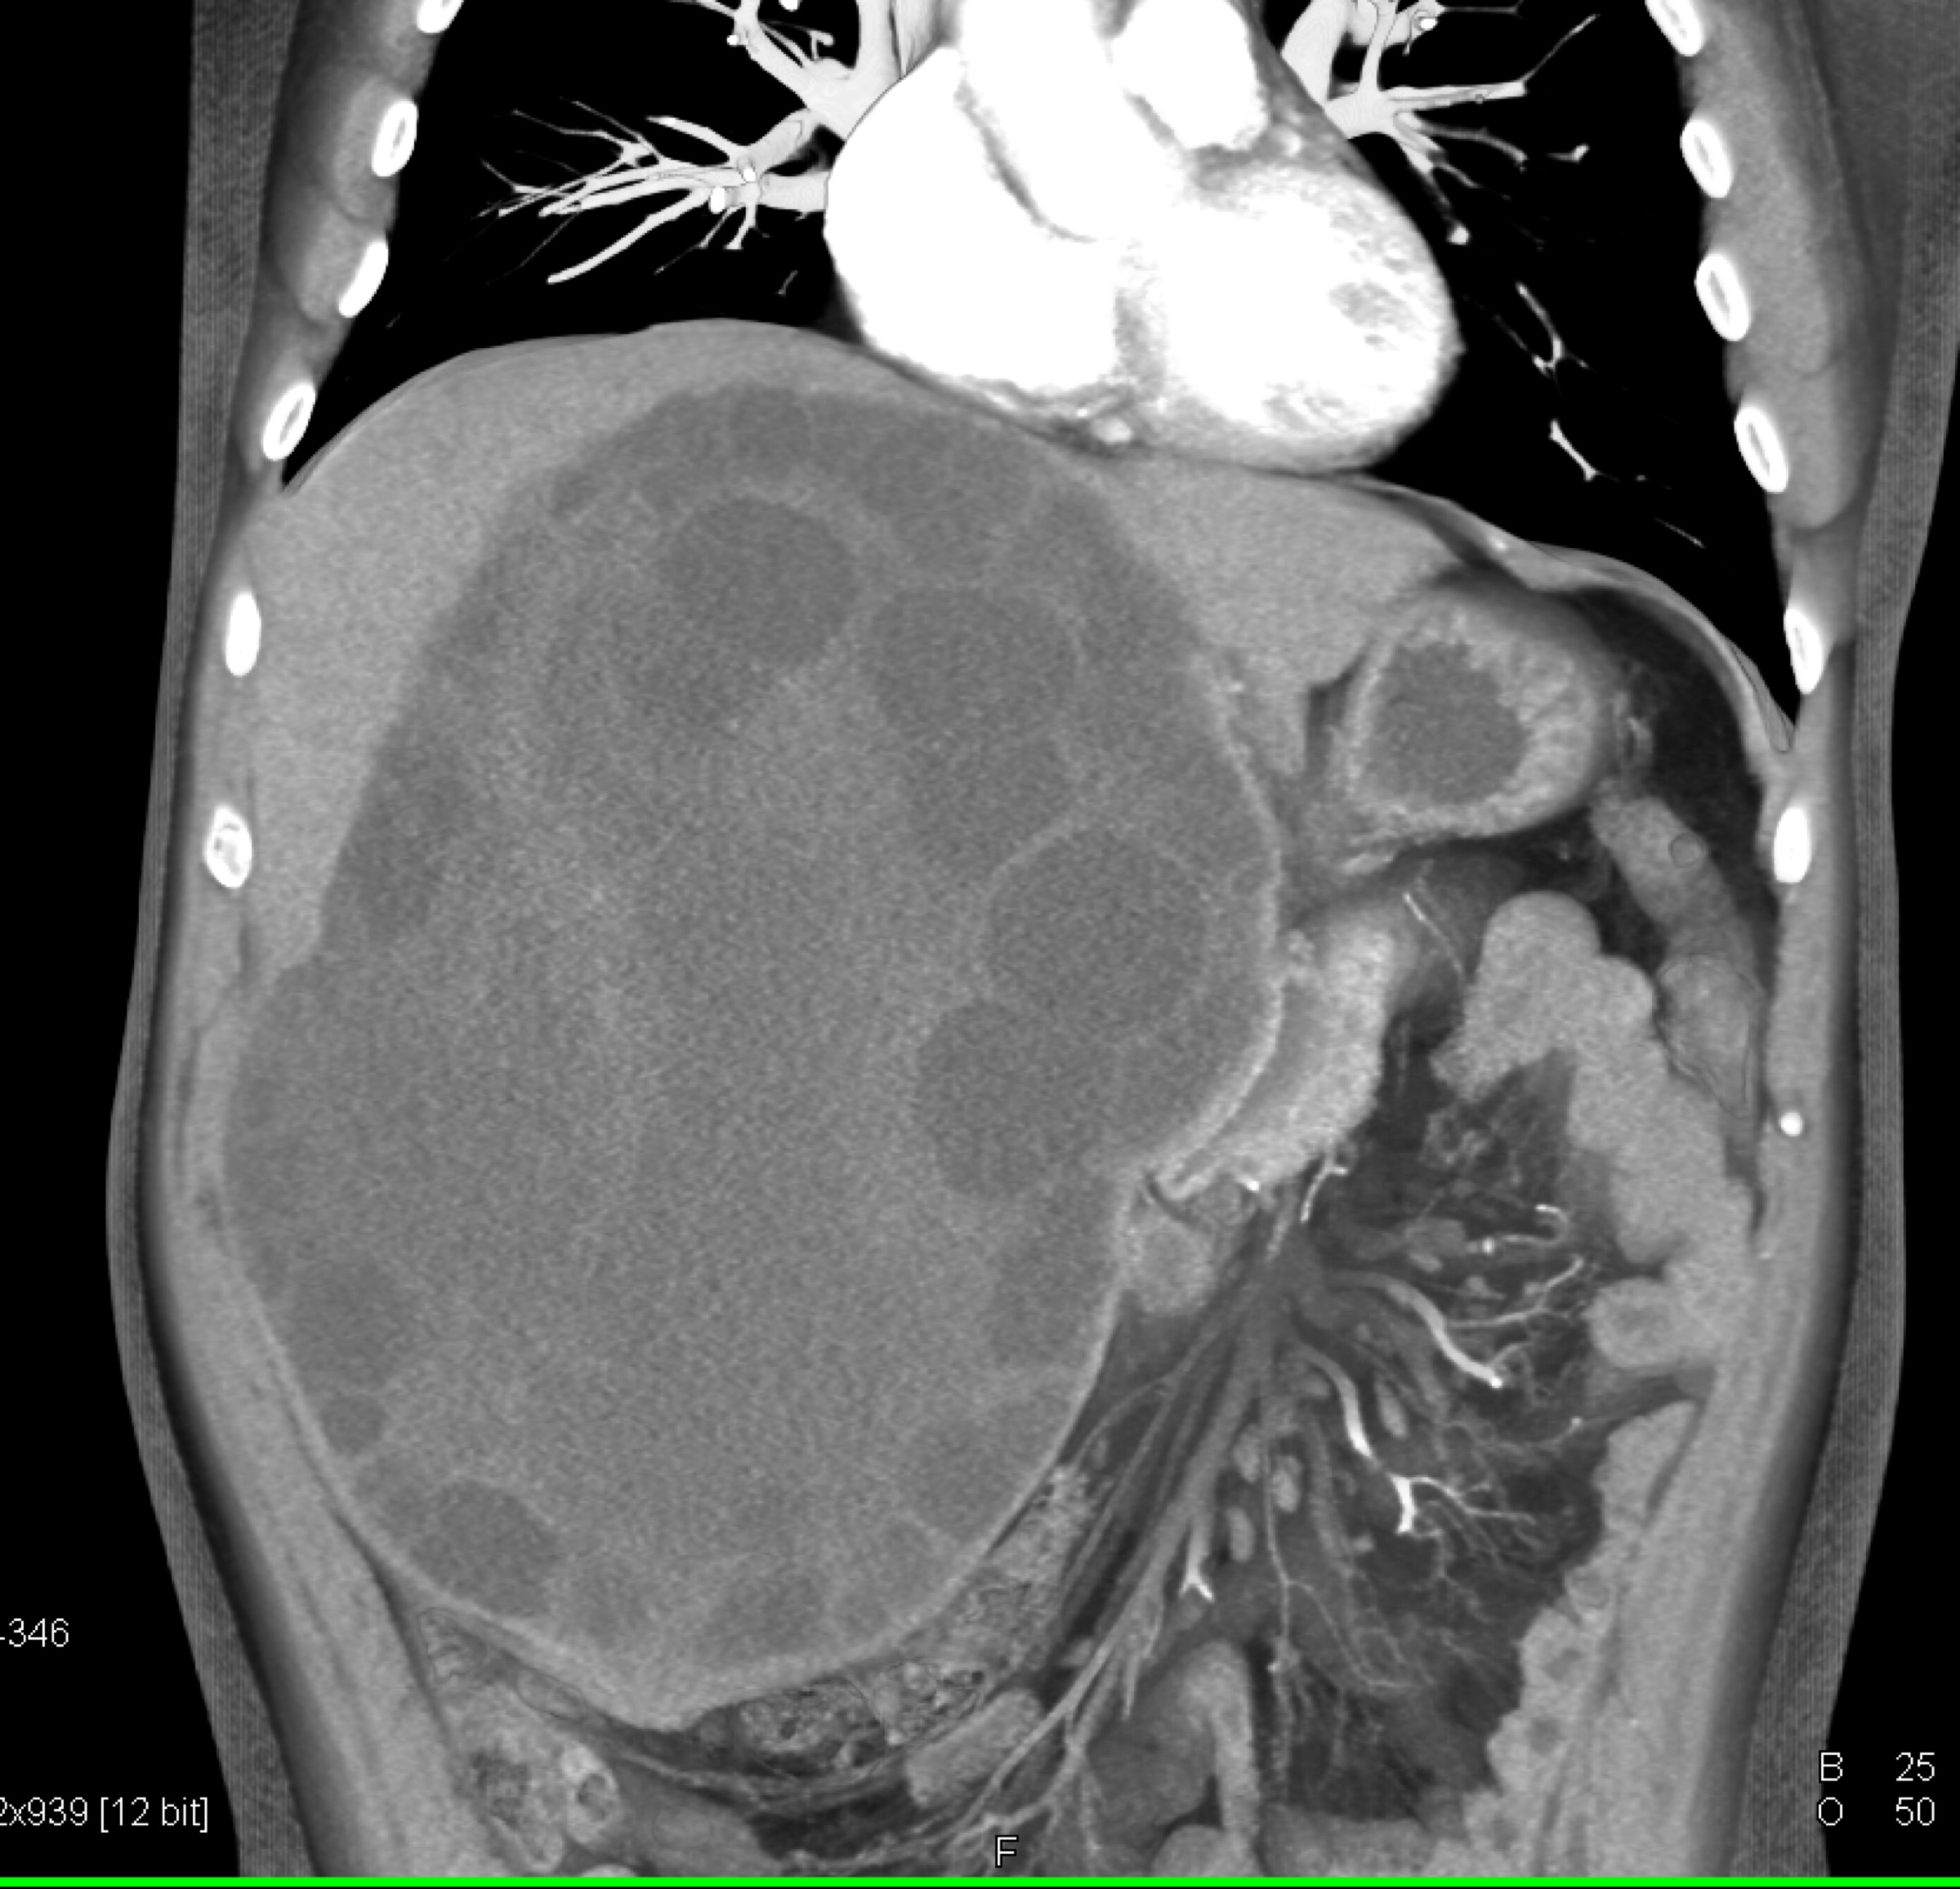

1) The most likely diagnosis in this patient with LUQ pain is?

adrenal myelolipoma

adrenal ganglioneuroma

adrenal adenoma

pheochromocytoma